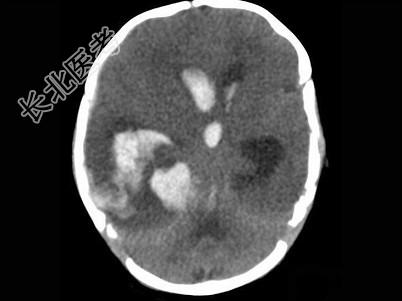

- 单项选择题男,刚满月, 突然发现不进食,昏睡, 无家族遗传病史,结合图像, 最可能的诊断是 ( )

A、脑膜炎

B、脑出血

C、脑脓肿

D、颅内动脉瘤

E、脑梗死